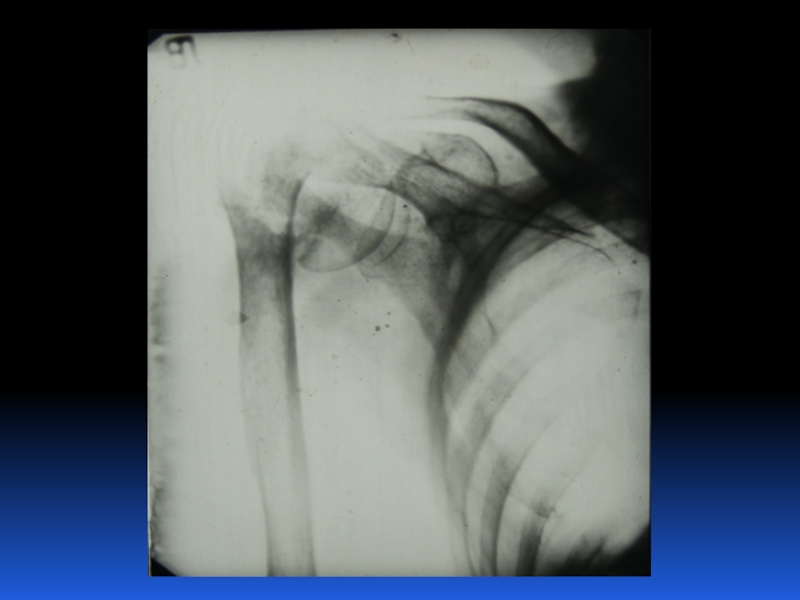

Остеопороз – это системное заболевание скелета, характеризующееся снижением костной массы и нарушением микроархитектоники костной ткани, с последующим увеличением хрупкости костей, со склонностью к патологическим переломам.

Слайд 2 Остеопороз – это системное заболевание скелета, характеризующееся снижением костной

массы и нарушением микроархитектоники костной ткани, с последующим увеличением хрупкости

костей, со склонностью к патологическим переломам.